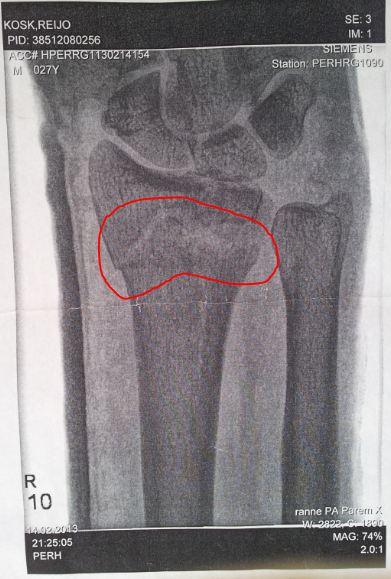

Murdsin siis ära randmeluu, küsisin operatsiooni arstilt peale kipsimaha võtmist, et kaua ma siis poksida ( tegelesin taipoksiga ) ja jõusaali teha ei tohi ? Arst vastas, et kui käe liikuma saad võid kõike teha kuna luu on paranenud ja vaja ainult käsi liikuma saada. Samuti soovitas ka füsioterapeuti kes andis siis vastavad harjutused. Küsisin siis ka terapeudilt, et kaua ma siis poksida ei saa ja kuidas oleks jõusaalid. Terapeut vastas, et poksida ei soovitaks kusagil 6 kuud ja jõusaali kohta ei osanud öelda, lubas vaid ujumas ja jooksmas käia.

Lisasin ka pildi kust luu katki oli, et ehk on abiks vastamisel.